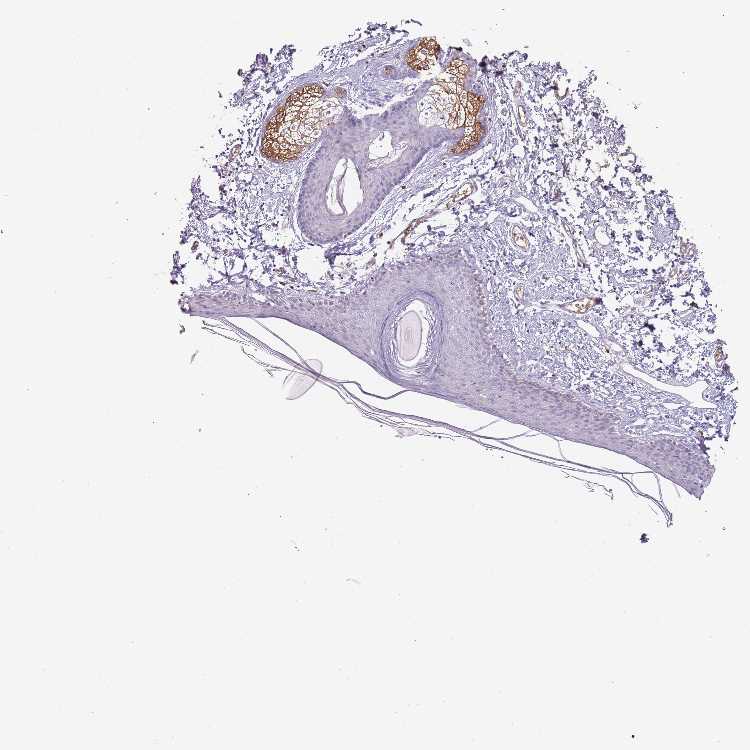

SKIN 2 - Antibody stainingi

Antibody staining in the annotated cell types in the current human tissue is reported as not detected, low, medium, or high, based on conventional immunohistochemistry profiling in selected tissues. This score is based on the combination of the staining intensity and fraction of stained cells.

Each image is clickable and will lead to virtual microscopy that enables deeper exploration of all samples and also displays staining intensity scores, fraction scores and subcellular localization as well as patient and tissue information for each sample.

Antibody HPA037763Antibody HPA037764Antibody CAB026170

Epidermal cells Not detectedNot detectedNot detected